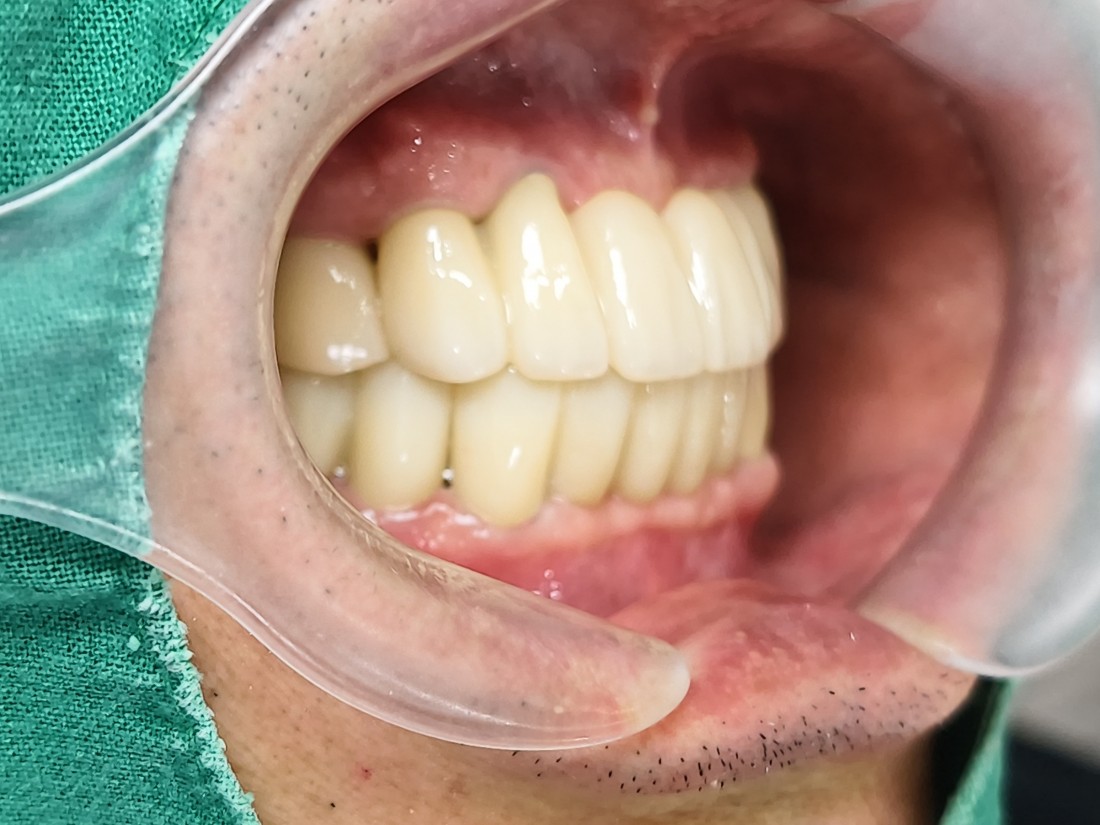

단 두 번의 수술만으로

광주 전체임플란트

완성할 수 있는 비결은

광주 전체임플란트 치과에서는

전체임플란트를 완성하고 있습니다.

자동차가 네비게이션을 따라

정확한 목적지에 도착하듯,

디지털가이드 임플란트를 활용하여

미리 임플란트를 3D 가이드로 제작하기 때문에

정확한 깊이, 정확한 위치에

임플란트 식립이 가능합니다.

광주 전체임플란트를 디지털가이드 임플란트로

완성하고 있기 때문에

잇몸절개를 하지 않거나 (무절개) 혹은

최소한으로만 절개하고 있어서

임플란트 수술 시간이 짧으며,

붓기 / 출혈 / 통증이 매우 줄어듭니다.